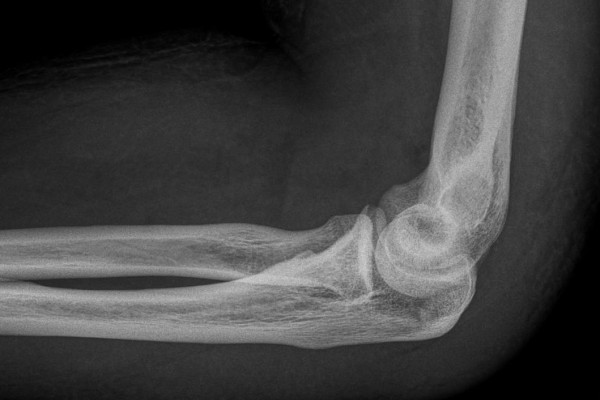

Tennis elbow or epicondylitis